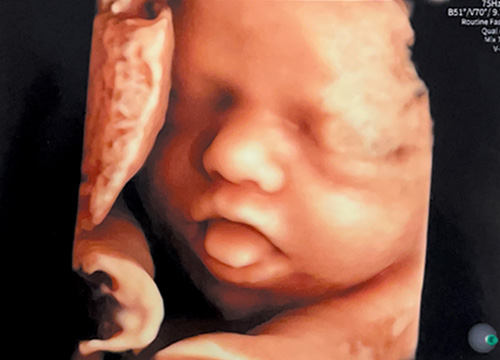

《 超音波検診 》

当院では4D超音波診断装置を導入しております。リアルタイムでお腹の赤ちゃんの様子がご覧いただけます。又、超音波検査で撮影された胎児の成長記録をUSBやSDカードに収録してお渡しするサービスも実施しています。但し、セキュリティの観点上、USBとSDカードは当院にてご購入いただいたものに限らせていただきます。

GE最新エコーを導入しており、胎児の血流情報も高感度で描写するパワードプラも備えています。